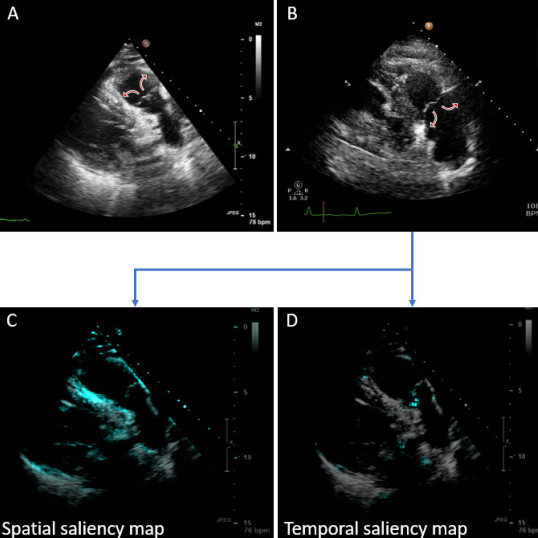

Echocardiogram interpretation - LINK

James developed a system which is able to analyse video clips taking during echocardiogram scans, to identify which anatomical structures are present. His novel approached more than halved the error rate of previous solutions.